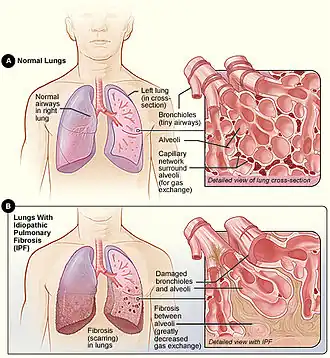

| A Figura A mostra a localização dos pulmões e das vias aéreas no corpo. A imagem inserida mostra uma visão detalhada das vias aéreas e dos sacos aéreos do pulmão em seção transversal. A Figura B mostra a fibrose (cicatrização) nos pulmões. A imagem inserida mostra uma visão detalhada da fibrose e como ela danifica as vias aéreas e os sacos aéreos.[1] | |

A fibrose pulmonar idiopática (FPI), ou (anteriormente[5]) alveolite fibrosante, é uma doença rara e progressiva do sistema respiratório, caracterizada pelo espessamento e enrijecimento do tecido pulmonar, associado à formação de tecido cicatricial. É um tipo de doença fibrose pulmonar crônica caracterizada por um declínio progressivo e irreversível da função pulmonar.[3][4] O tecido dos pulmões torna-se espesso e rígido, o que afeta o tecido que circunda os sacos aéreos nos pulmões.[6] Os sintomas geralmente incluem o início gradual de falta de ar e tosse seca.[1] Outras alterações podem incluir sensação de cansaço e unhas dos pés e das mãos anormalmente grandes e em formato de cúpula (baqueteameto dos digital).[1] As complicações podem incluir hipertensão pulmonar, insuficiência cardíaca, pneumonia ou embolia pulmonar.[1]

A causa é desconhecida, daí o termo idiopático.[2] Os fatores de risco incluem o tabagismo, a doença de refluxo gastroesofágico (DRGE), certas viroses e predisposição genética.[1] O mecanismo subjacente envolve a formação de cicatrizes nos pulmões (fibrose).[1] O diagnóstico requer a exclusão de outras possíveis causas.[3] Pode ser apoiado por uma tomografia computadorizada de alta resolução (TCAR) ou biópsia pulmonar que mostre pneumonia intersticial usual (PIU).[3] É um tipo de doença pulmonar intersticial (DPI).[3]